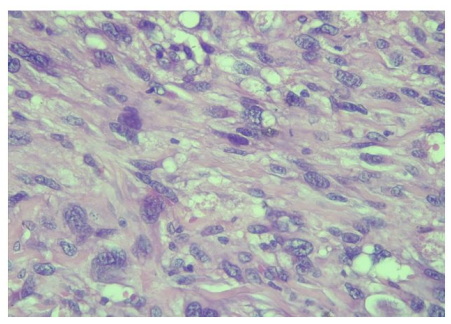

| Figure 2: (HE x 400): ovoid or fusiform sarcomatous cells with distinct cytonuclear atypia |

The pelvic MRI revealed a heterogeneous mass of bulbo membranous urethra and no lymph nodes metastatic. Thoraco-abdominal scan showed no distal metastatic disease. A bulbo-urethrectomy with removal bulbo-cavernous muscles and perineal skin was performed. Histological examination of urethrectomy specimen after inclusion, sectioning and haematein-eosin staining showed a connective tumour proliferation with a fasciculated and storiform architecture. Tumour cells are pleomorphic with cytonuclear atypia, and a mitotic index evaluated at 3 mitoses per 10 fields at 400x magnification. Tumour cells were positive for vimentin on immunohistochemistry. Tumour cells were negative for S100, HMB45, Smooth muscle actin, CKAE1/AE3, MDM2, CD117, DOG1, CD34 and EMA. Fluorescent in situ hybridization did not have the synovialosarcoma-specific t (X; 18) translocation. Pathological examination concluded to an undifferentiated sarcoma of the urethra unclassifiable grade II according to the FNCLCC. (Figure 2).